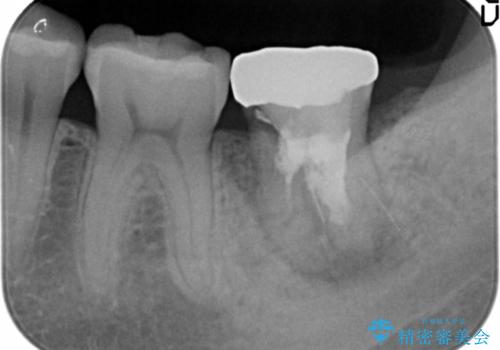

精査したところ、左下の奥歯にはひびが入っていて、保存不可能な状態でした。

割れている奥歯を抜去後左上の機能していない親知らずを移植し、生着したのち根管治療・補綴を行いました。

被せ物の種類:メタルボンドクラウン エコノミー フルベイク